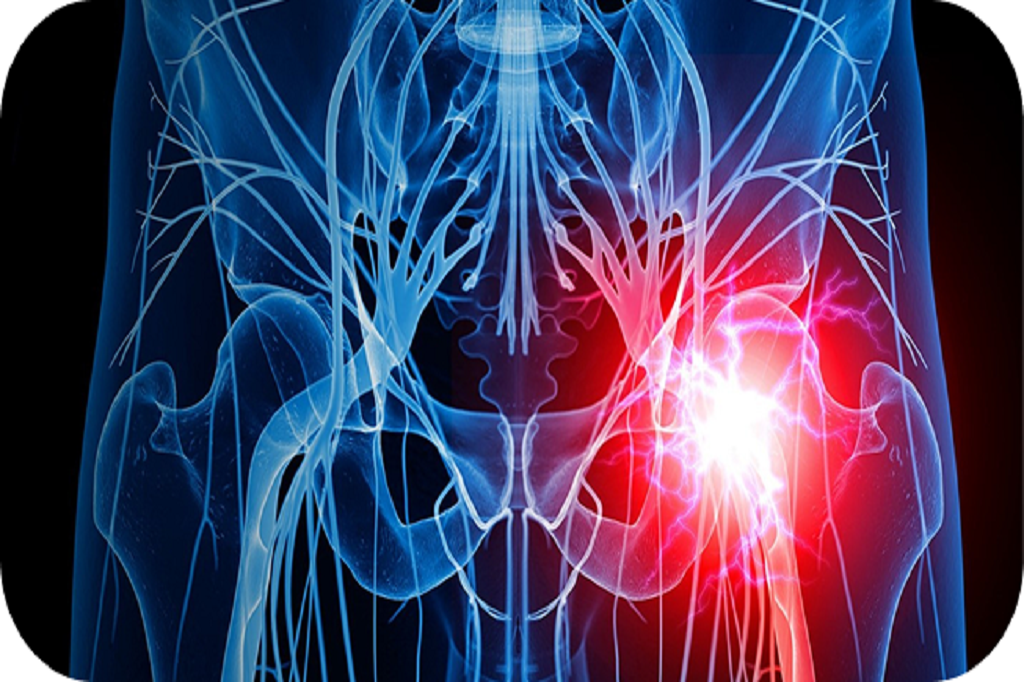

Scar tissue (adhesions) can sometimes form around spinal nerves after surgery, injury, or chronic inflammation. These adhesions may trap or irritate nerves, leading to persistent back, leg, or neck pain.

Persistent pain linked to nerve entrapment and inflammation

Reduces inflammation and nerve irritation

MRI or CT scans help identify adhesions.

MRI or CT scans help identify adhesions.